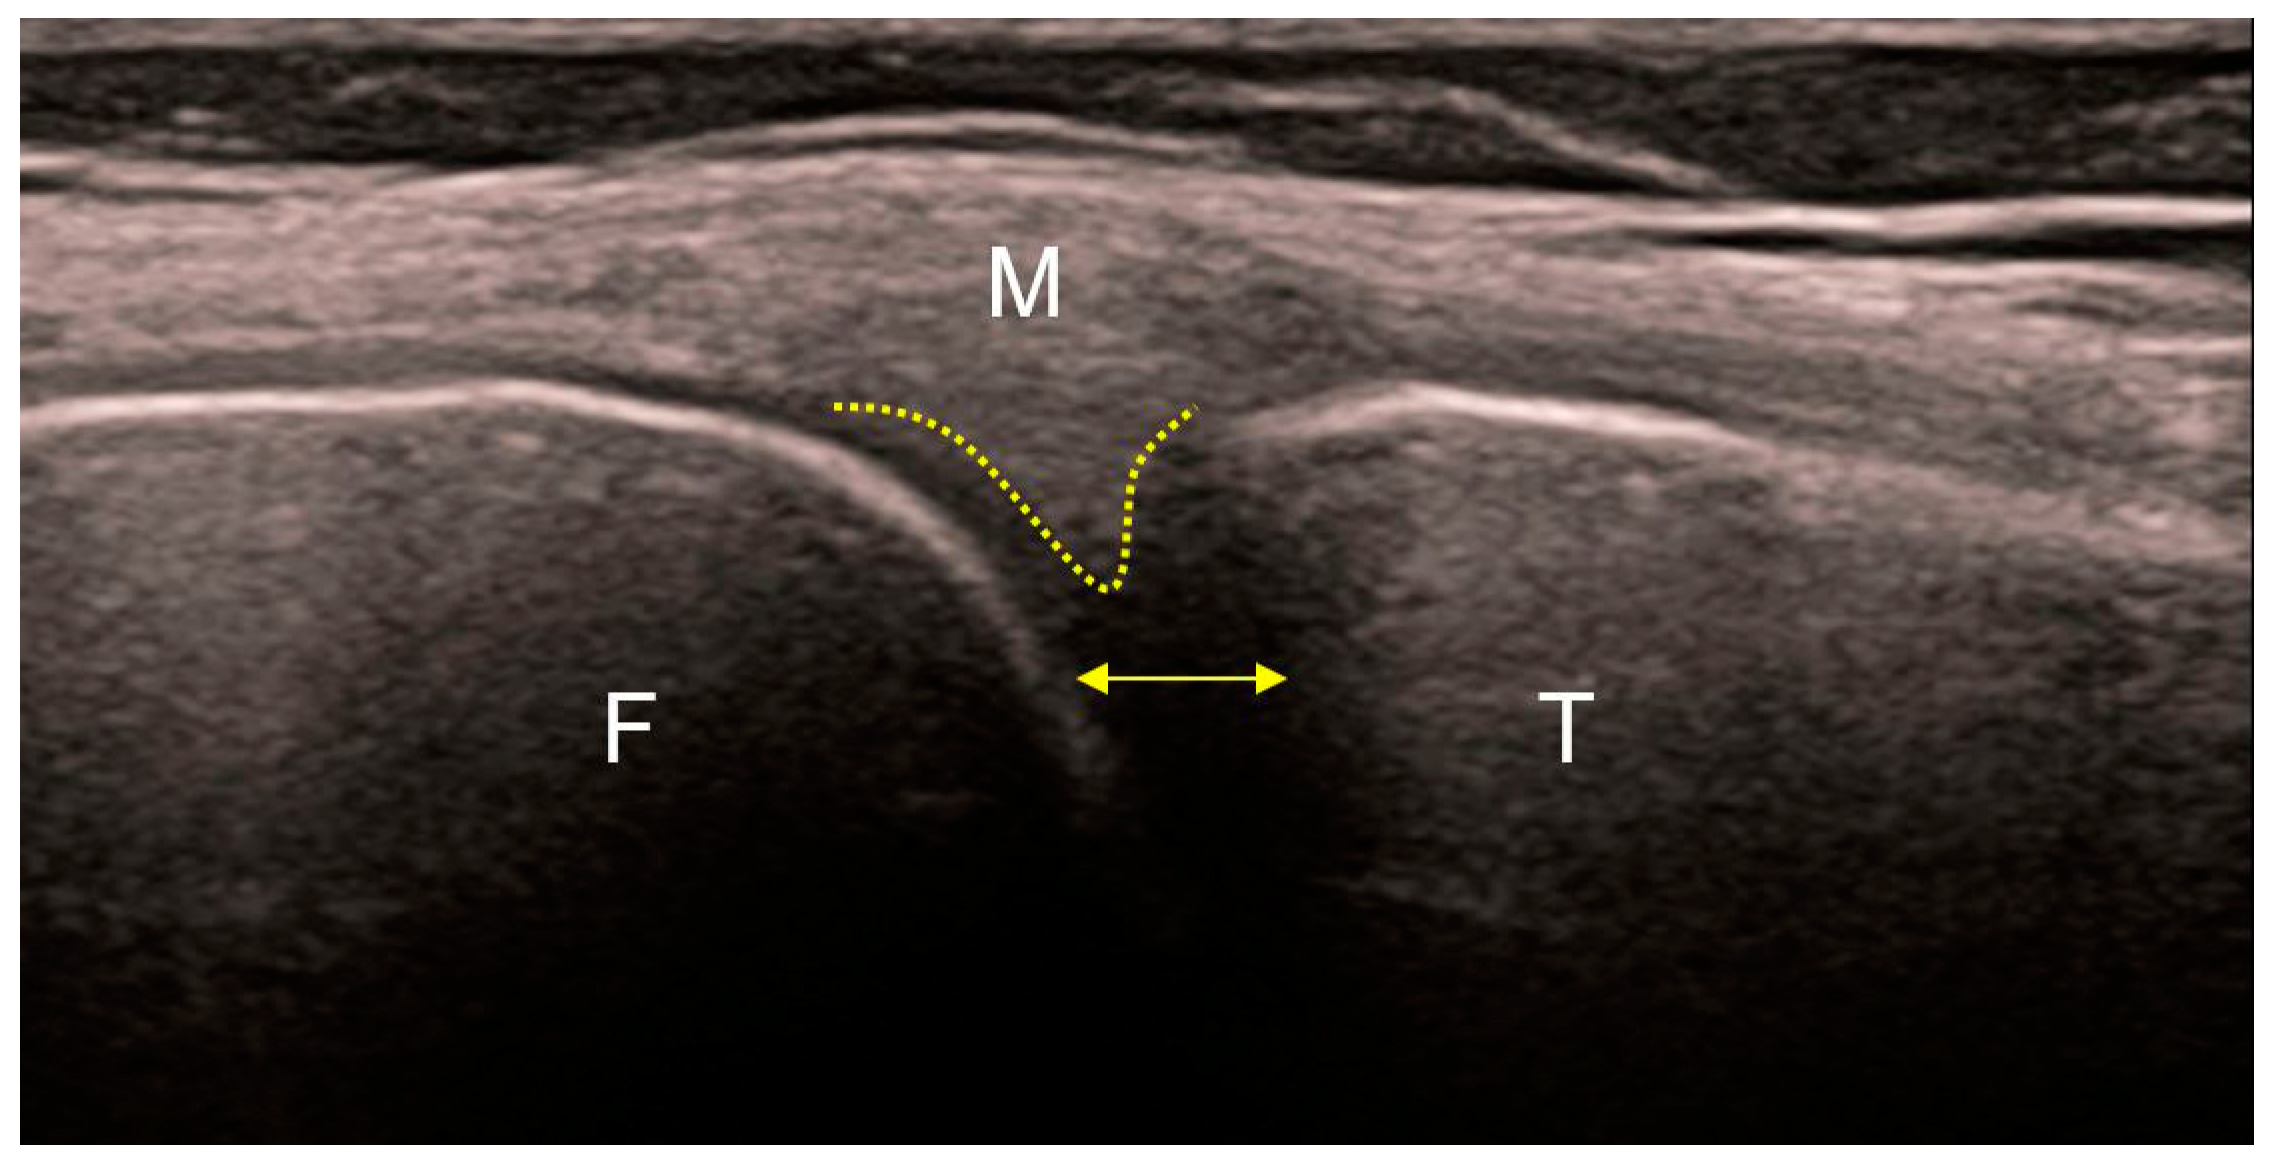

4. Radiological Characteristics of Osteoarthritis